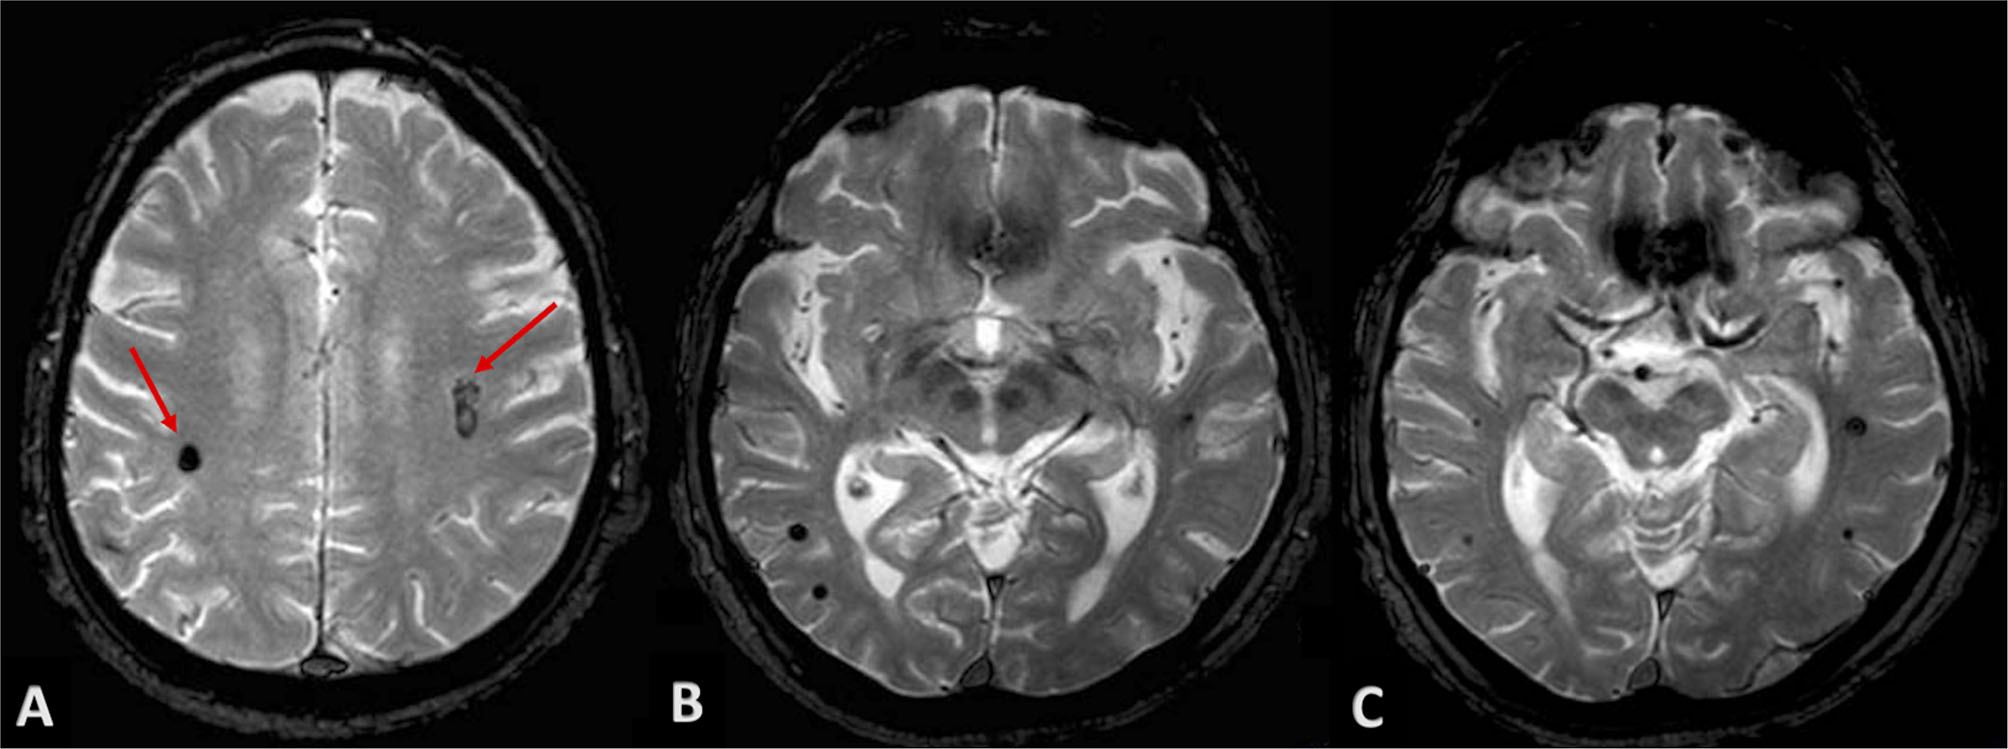

Neurological examination of patients at discharge was completely normalized. Due to the “atypical” locations of intraparenchymal hematomas, we performed a brain MRI at longitudinal follow-up in order to exclude non-hypertensive causes of bleeding. Gradient-echo T2*-weighted sequences revealed two small roundish lesions, in the anatomical site of bilateral subcortical hematomas, with minute central nucleus of methemoglobin and dark hemosiderin rim, and without surrounding edema, consistent with cavernous venous malformations (Figure 4A). Multiple similar but smaller cavernous angiomas were detected throughout subcortical white matter on both sides, particularly in temporal and occipital lobes, and in the area of basal ganglia (Figures 4B,C). On differential diagnosis, T2 and FLAIR sequences excluded findings suggestive of other conditions, as possible cerebral amyloid angiopathy; no evidence of significant subcortical leukoencephalopathy was detected besides lacunar microinfarcts in the region of basal ganglia bilaterally, and no signs consistent with superficial siderosis were detected.

Figure 4. Patient's MRI at follow-up. Gradient-echo T2*-weighted sequences revealed roundish lesions underlying well-known intraparenchymal hemorrhages (A, red arrows), with classic magnetic resonance appearance of cavernous venous malformations. (B,C) show multiple and similar lesions throughout subcortical white matter and basal ganglia, bilaterally.